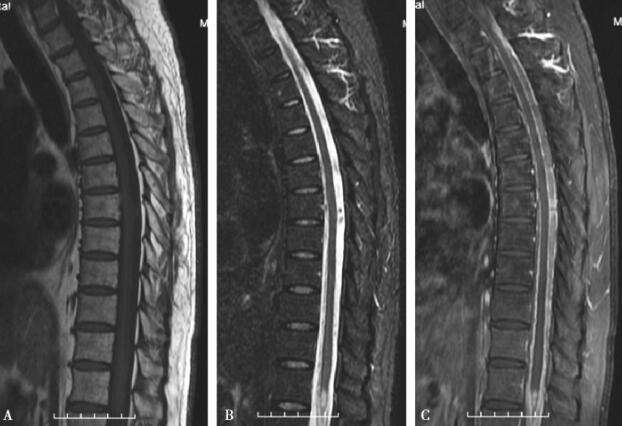

图3 胸髓异常信号,脊膜强化

A.胸髓MRI T1像;B.胸髓MRI T2像;C.胸髓MRI增强像。胸髓内可疑异常信号,广泛脊膜强化